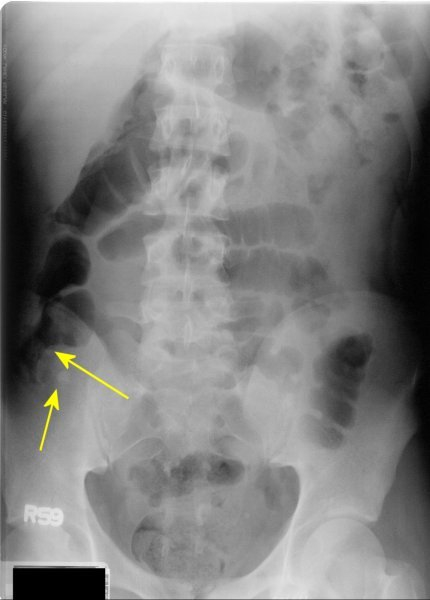

What is going on in this KUB?

This patient has an appendicolith and associated inflammation. The inflamed fat is pushing on the cecum, creating a divit in the bowel gas.